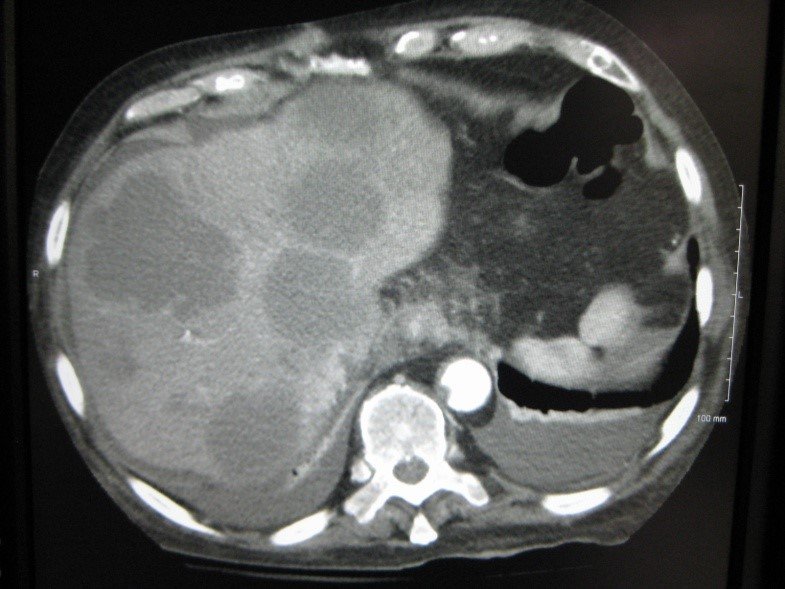

- Görüntüləmədə I seqment hipertrofiyası (yüksək şübhə əlaməti)

- Diaqnozu dəqiqləşdirmək üçün Qc venaları yoxlanılmalıdır. Bunun üçün dopler USM, KT-angioqrafiya, MRT-angioqrafiyalar və ya kontrastlı venoqrafiya edilir.

- Görüntüləmədə Qc venalarının trombotik tutulması diaqnozu dəqiqləşdirən əlamətdir.

- Görüntüləmədə qaraciyər venalarının tıxanması

Baddi-Kiari sindromu böyük qaraciyər venalarının tıxanması nəticəsində meydana gələn venoz durğunluqdur, qaraciyər venaları ilə yanaşı aşağı boş venada da tıxanma ola bilir. Tromboz, fibroz, membran və infiltrasiya (şişlər, iltihab) ən çox rast gələn səbəbləridr. Erkən mərhələlərdə kəskin hepatit və kəskin qaraciyər yetməzliyi, xroniki mərhələdə sirroz və PH meydana gələ bilir. Diaqnozu üçün tomoqrafiya və kontrastlı angioqrafiya lazım gəlir, Qc venalarının trombotik tutulması diaqnozu təsdiqləyir. digər xarakterik əlaməti birinci seqmentin hipertrofiyasıdır. Erkən mərhələdə dekompressiya (cərrahi və stend) sirroz əmələ gəldikdə isə transplantasiya ön planda tutulur.

Qaraciyər venalarının görünməməsi, kontrastlaşmaması və ya trombla tıxanması.

- Görüntüləmədə qaraciyər venalarının tıxanması, I seqment hipertrofiyası ola bilər (xroniki forma);